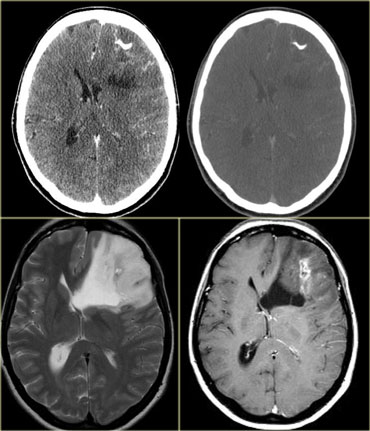

GBM with patchy enhancement and cystic component with ring enhancement GBM with patchy enhancement and cystic component with ring enhancement

Patchy enhancement can be seen in:

• Metastases

• Oligodendroglioma

• Glioblastoma multiforme

• Radiation necrosis

On the left is an example of a glioblastoma multiforme (GBM).

The enhancement indicates that this is a high-grade tumor, but only parts of it enhance.

Notice that there is also a cystic component with ring enhancement.

The tumor cells probably extend beyond the area of edema as seen on the FLAIR image.

This is because gliomas grow infiltratively into normal brain - initially without any MR changes.

Patchy enhancement (2)

On the left are images of a tumor located in the right hemisphere.

Although is a large tumor, the mass-effect is limited.

This indicates that there is marked infiltrative growth, a characteristic typical for gliomas.

Notice the heterogeneity on both T2WI and FLAIR.

There is patchy enhancement.

All these findings are typical for a GBM.

Virtually no other tumor behaves in this way.